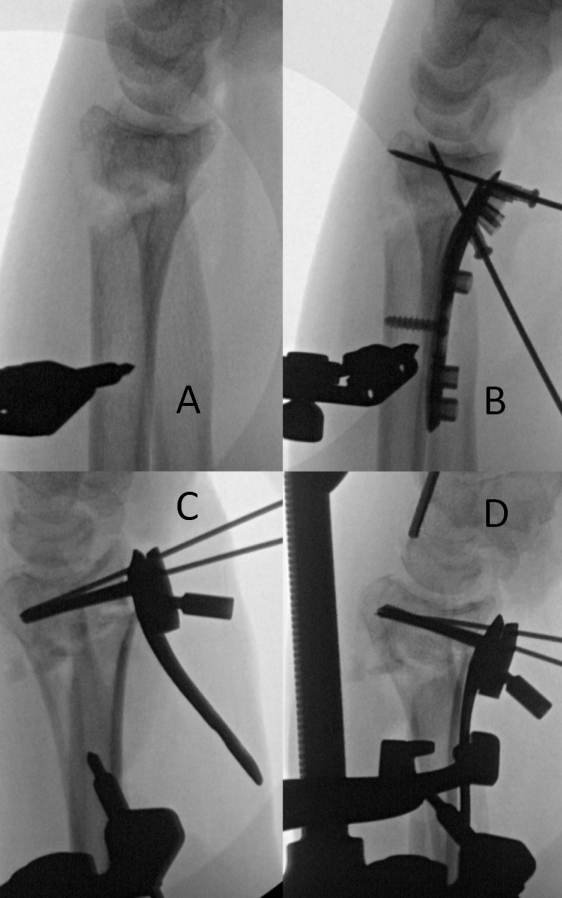

准备压缩/牵引装置,即“迷你牵引器”(图1A)。装置含3个锁定夹,初始状态下均松开。提供2.0 mm、2.5 mm和3.0 mm规格的固定针。作者倾向于使用2.5 mm螺纹尖端针,因其在牵引时不易弯曲。将2.5 mm固定套筒部分旋入牵引臂的固定孔。随后,在桡骨干距桡骨茎突约四横指处,由桡侧向尺侧置入2.5 mm螺纹尖端针。触诊示指掌骨桡侧中心,作小切口,分离组织,将2.5 mm螺纹尖端针置入示指掌骨干(图1B)。前臂旋后位下,腕部置于4块纵向叠放的毛巾上,自腕关节向远端支撑手部(图1C)。毛巾堆叠有助于恢复掌倾角,同时为牵引器提供操作空间。为调整牵引臂间距,将切换开关置于“牵引(DISTR)”或“压缩(COMP)”位,旋转翼形螺栓。将套筒滑至骨面,使用套筒手柄将克氏针固定。轻柔按压桡骨干以初步恢复掌倾角,随后锁紧三个锁定夹(图1D)。

图1. 桡骨远端迷你牵引器的组装。(A)压缩/牵引装置(Depuy Synthes);(B)触诊示指掌骨桡侧面;(C)手部下方垫4块折叠毛巾以辅助恢复掌倾角;(D)装置长臂朝向床面放置,所有铰链锁定。

C臂机就位,在透视引导下,通过韧带牵引复位术调整腕部至正确的桡骨高度(图2)。确认桡骨高度后,术者可选择用碎屑状松质骨同种异体骨填充干骺端骨缺损。

图2. 使用牵引器“调整”桡骨高度和桡偏角的前后透视示例(A、C为牵引前,B、D为牵引后)。